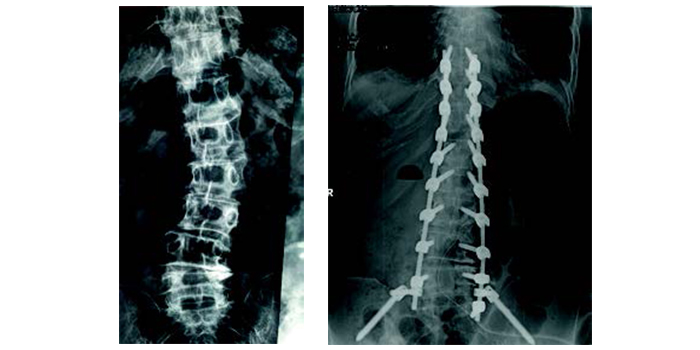

Για πρώτη φορά στην Ελλάδα, το 2016, εφαρμόστηκε με επιτυχία στο Metropolitan Hospital το σύστημα 3D απεικόνισης/χειρουργικής πλοήγησης σε παιδιά με σκολίωση.

Το σύστημα επέτρεψε την τοποθέτηση των εμφυτευμάτων σε πραγματικό χρόνο με την ακρίβεια αξονικού τομογράφου. Η ακρίβεια αυτή εκμηδενίζει την πιθανότητα ιατρικού λάθους και την πρόκληση μόνιμων νευρολογικών βλαβών, ενώ παράλληλα παρέχει ένα εξαιρετικό αισθητικό αποτέλεσμα, πράγμα σημαντικό για τις κοπέλες που πάσχουν από σκολίωση. Το σύστημα χρησιμοποιείται σε παιδιά και ενήλικες με κύφωση ή σκολίωση.

Χειρουργικές εναλλακτικές

Για τα παιδιά και τους εφήβους, η χειρουργική αντιμετώπιση της σκολίωσης προτείνεται για καμπύλες που έχουν ξεπεράσει τις 45 μοίρες. Στην περίπτωση που σκολιώσεις αυτού του μεγέθους αφεθούν χωρίς χειρουργική αντιμετώπιση θα συνεχίσουν να επιδεινώνoνται ακόμη και μετά την ολοκλήρωση της σκελετικής ωρίμανσης, με αποτέλεσμα το χρόνιο πόνο, την αναπνευστική δυσλειτουργία και τις ψυχοκοινωνικές επιπτώσεις, ιδιαίτερα για τα κορίτσια. Δυστυχώς, όταν η σκολίωση ξεπεράσει τις 45 μοίρες ο κηδεμόνας δεν είναι πλέον αποτελεσματικός. Για έναν έφηβο με κύφωση Scheuermann, εάν η κύφωση συνεχίζει να εξελίσσεται φτάνοντας τις 70 μοίρες παρά τη χρήση του κηδεμόνα και το παιδί παραπονείται για συνοδό πόνο, η χειρουργική επέμβαση αποτελεί τη θεραπεία εκλογής.

Η αντιμετώπιση στους ενήλικους είναι κατά κανόνα χειρουργική. Διαδερμικές και αναίμακτες επεμβάσεις μπορούν να βοηθήσουν στη διόρθωση της κύφωσης και την αντιμετώπιση του πόνου ενός οστεοπορωτικού κατάγματος. Η σκολίωση των ενηλίκων θα πρέπει να διορθωθεί χειρουργικά όταν συνδυάζεται με πόνο στη μέση ή στα πόδια, που περιορίζει τις καθημερινές δραστηριότητες και μειώνει την ποιότητα ζωής.